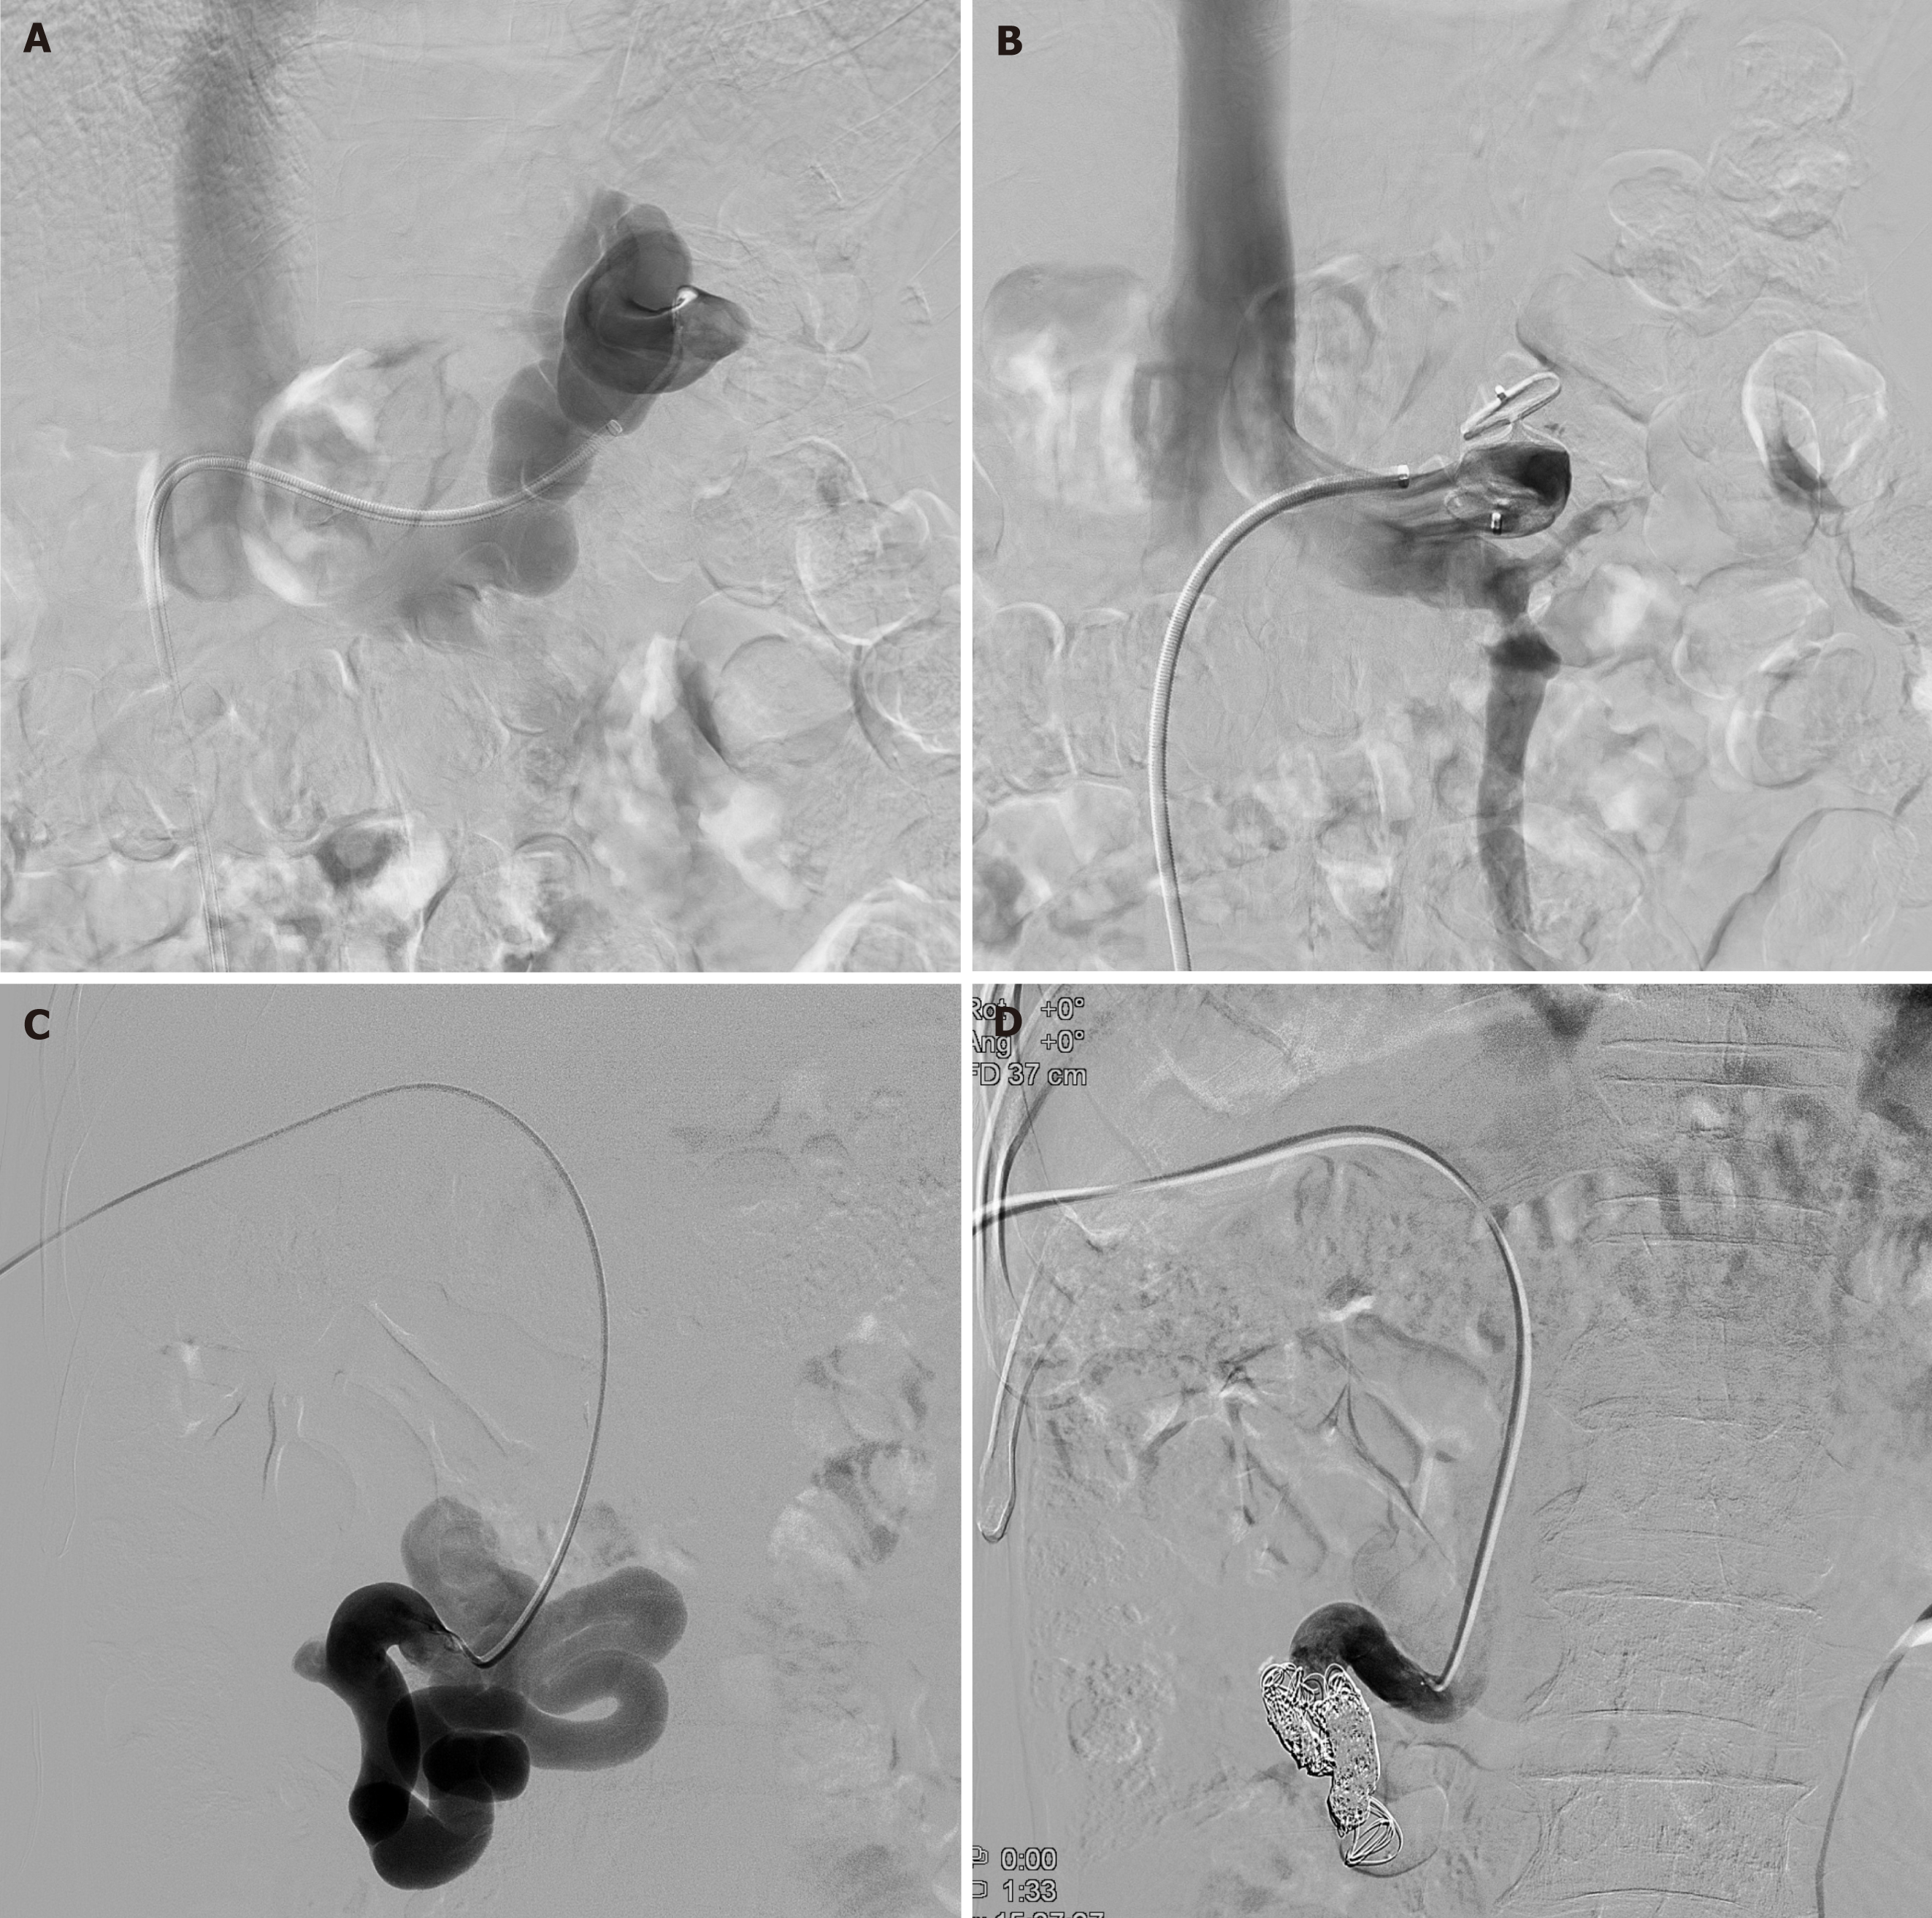

Figure 3 Angiographic images of splenorenal shunt embolization and mesocaval shunt embolization.

A: After a 9-F vascular sheath was placed in the splenorenal shunt, the shunt was accessed coaxially using a 5-F cobra catheter; B: The vascular plug was deployed at the narrowest region of the splenorenal shunt through the vascular sheath and completion venography showed complete occlusion of the splenorenal shunt; C: Transhepatic superior mesenteric venogram showed the large size of mesocaval shunt; D: Coil placement showed complete closure of mesocaval shunt.